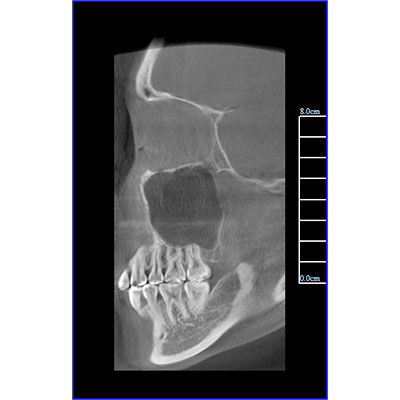

專有三維重建算法,可提供任意位置高清斷層影像。

通過三維容積影像,提取高清口腔全景影像。